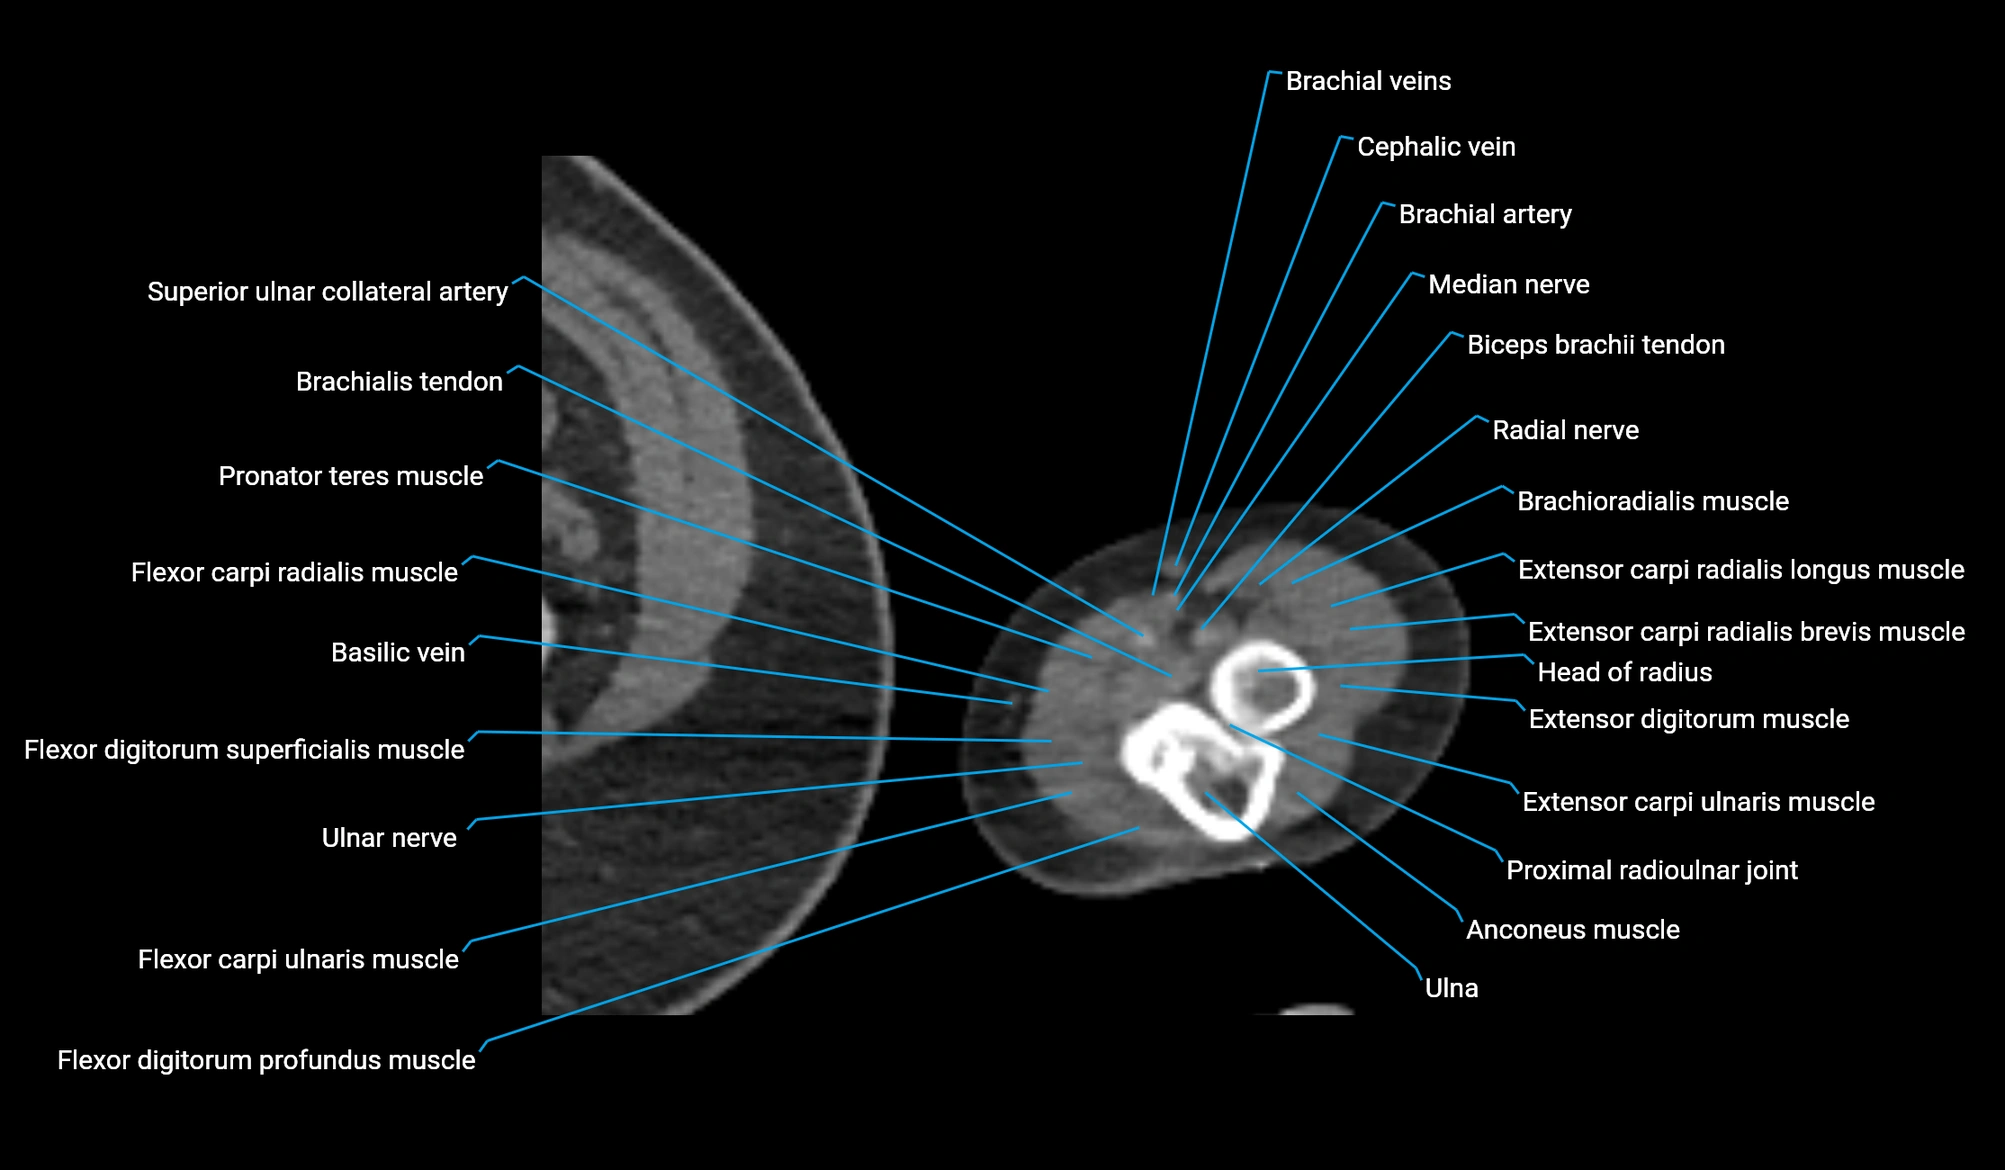

- Basilic vein

- Cephalic vein

- Extensor carpi radialis brevis muscle

- Extensor carpi radialis longus muscle

- Extensor carpi ulnaris muscle

- Extensor digitorum muscle

- Flexor carpi radialis muscle

- Flexor carpi ulnaris muscle

- Flexor digitorum profundus muscle

- Flexor digitorum superficialis muscle

- Head of radius

- Median nerve

- Proximal radioulnar joint

- Radial nerve